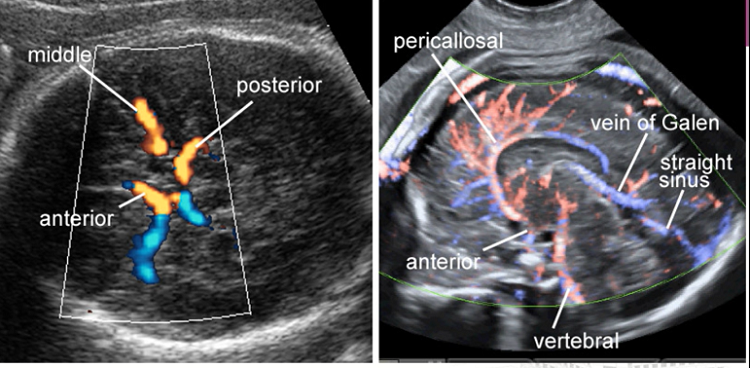

新生儿颅脑超声可以清晰显示新生儿颅内的各种结构及血管的情况。

正常颅内血管

6.脑血管疾病的检查没有年龄限制。

新生儿颅内出血、缺氧缺血性脑病、脑室周围白质软化、新生儿脑梗死、颅脑先天性异常、脑积水、颅内感染、颅内占位性病变、颅脑血管病变等。